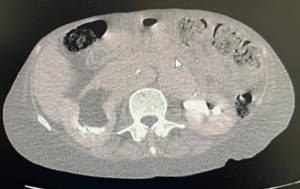

Paciente feminina, 68 anos, negra, que vive com HIV há cerca de 18 anos em tratamento irregular estava internada em unidade hospitalar para investigação de neoplasia linfoproliferativa e durante investigação foi solicitada tomografia computadorizada de abdome e pelve (relato de grande ureterohidronefrose direita e provável compressão ureteral extrínseca ao nível dos vasos ilíacos, com eliminação de contraste do ureter esquerdo em fase tardia), sendo pedido parecer a urologia.